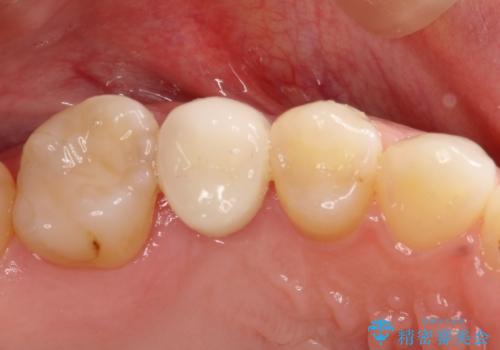

隙間が気になる。審美性の高いインプラント治療

- 欠損歯があり、隙間があることを主訴に来院されました。

術前に矯正治療(インビザライン)を行いインプラントにて欠損補綴を行なっております。

術前に矯正治療を行うことで適正な位置でのインプラント治療が行えました。